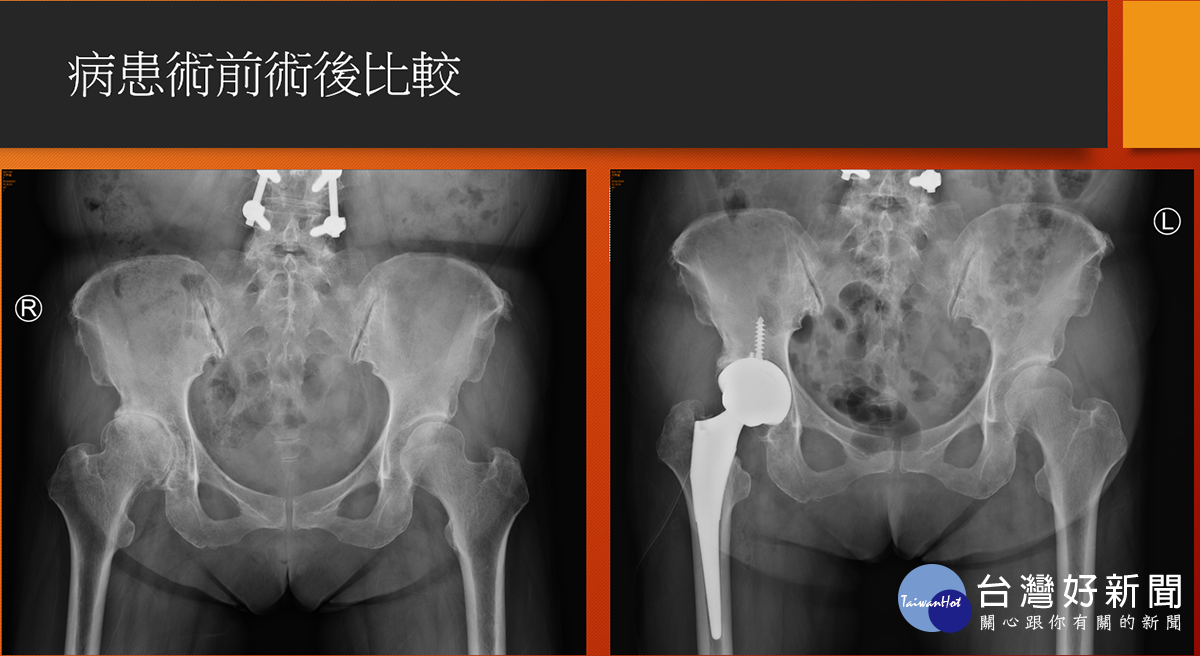

病人術前術後X光比較。(圖/七賢脊椎外科醫院提供)

高雄市一名63歲謝姓婦女在20多年前一場車禍, 造成右腳無法出力,中間歷經中醫針灸、骨傷、復健治療, 但因美髮師工作得長期站立,依靠左腳出力支撐, 卻又讓左腳開始產生疼痛, 直至去年底才在骨科門診中發現雙邊髖關節都已磨損嚴重, 醫師建議以“正前開”髖部手術,先處理持續疼痛感的左邊髖關節, 術後謝女士表示幾乎沒有疼痛感, 並在今年又另安排右邊髖關節置換手術, 順利解決謝女士多年的髖部疼痛不適。

七賢脊椎外科醫院骨關節科副院長楊華偉醫師說明, 一般在面臨人工髖節置換手術後的病人常遇到有疼痛、長短腳、 脫臼、復原時間較長等問題,但若是以正前開手術都可克服, 只是醫師在手術困難度上相對提高, 過去在國外文獻上統計之病人術後效果也非常良好, 目前在本院之案例也已達50人, 追蹤病人對於術後反應均以正面回饋。

楊華偉強調,正前開陶瓷人工髖關節手術, 其中陶瓷可解決磨損與腐蝕問題,也大幅降低二次開刀機會, 另外正前開之先進手術更能進一步改善常見術後之疼痛與復原時間問 題。而正前開手術對於嚴重骨鬆與體重過重BMI大於40的病人較 不適合,目前針對正前開之手術費用是健保給付範圍內, 除置換之髖關節自費材料外,不需有其他額外手術費用負擔。 有任何髖關節治療問題定要找專業骨科醫師做諮詢, 以選擇最適合個人的治療方式。